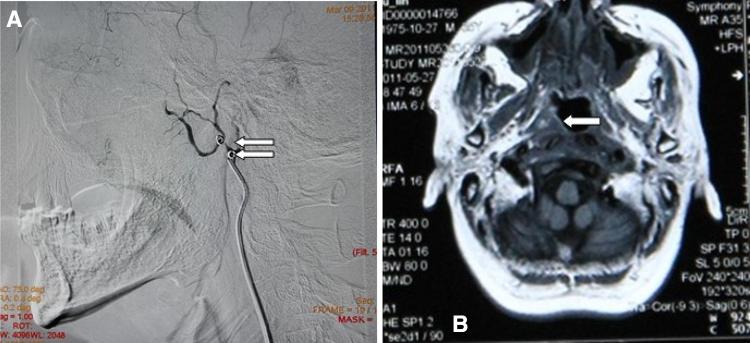

To report clinical manifestations, bleeding point localization, and outcomes of management in 16 patients with 16 instances of intractable epistaxis after radiation therapy for nasopharyngeal carcinoma. Retrospective chart review of 16 patients with nasopharyngeal carcinoma (mean age 52.06 ± 14.37 years) with 16 instances of intractable epistaxis during the past 5 years, whose diagnosis was confirmed by angiography (n = 10) or MRI/CT imaging studies and clinical manifestations (n = 6). The mean radiation dose to the affected carotid artery was 101.37 ± 34.85 Gy. Bleeding points were detected in the internal carotid artery (n = 8) or external carotid artery (n = 8). Detachable balloons were used in one affected artery for vascular occlusion; six were treated using an absorbable gelatin sponge (n = 4) or microcoils (diameter 1 mm) (n = 2). Endovascular embolization was successful in seven radiation carotid blowout syndromes with cessation of hemorrhage. One patient underwent external carotid artery ligation and one patient recovered without treatment. The clinical follow-up was 3 months. Therapeutic endovascular embolization of intractable epistaxis is both efficient and safe. It should be considered as the primary treatment modality in intractable epistaxis of nasopharyngeal carcinoma.